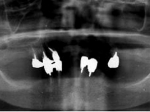

術前レントゲン